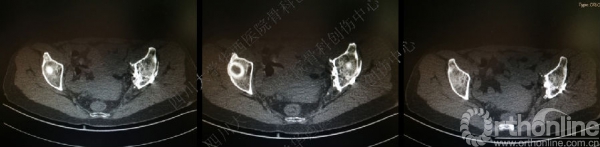

术后CT

术后冠状位及横切面CT扫描,负重区解剖复位

术后CT也证实骨盆形态正常。